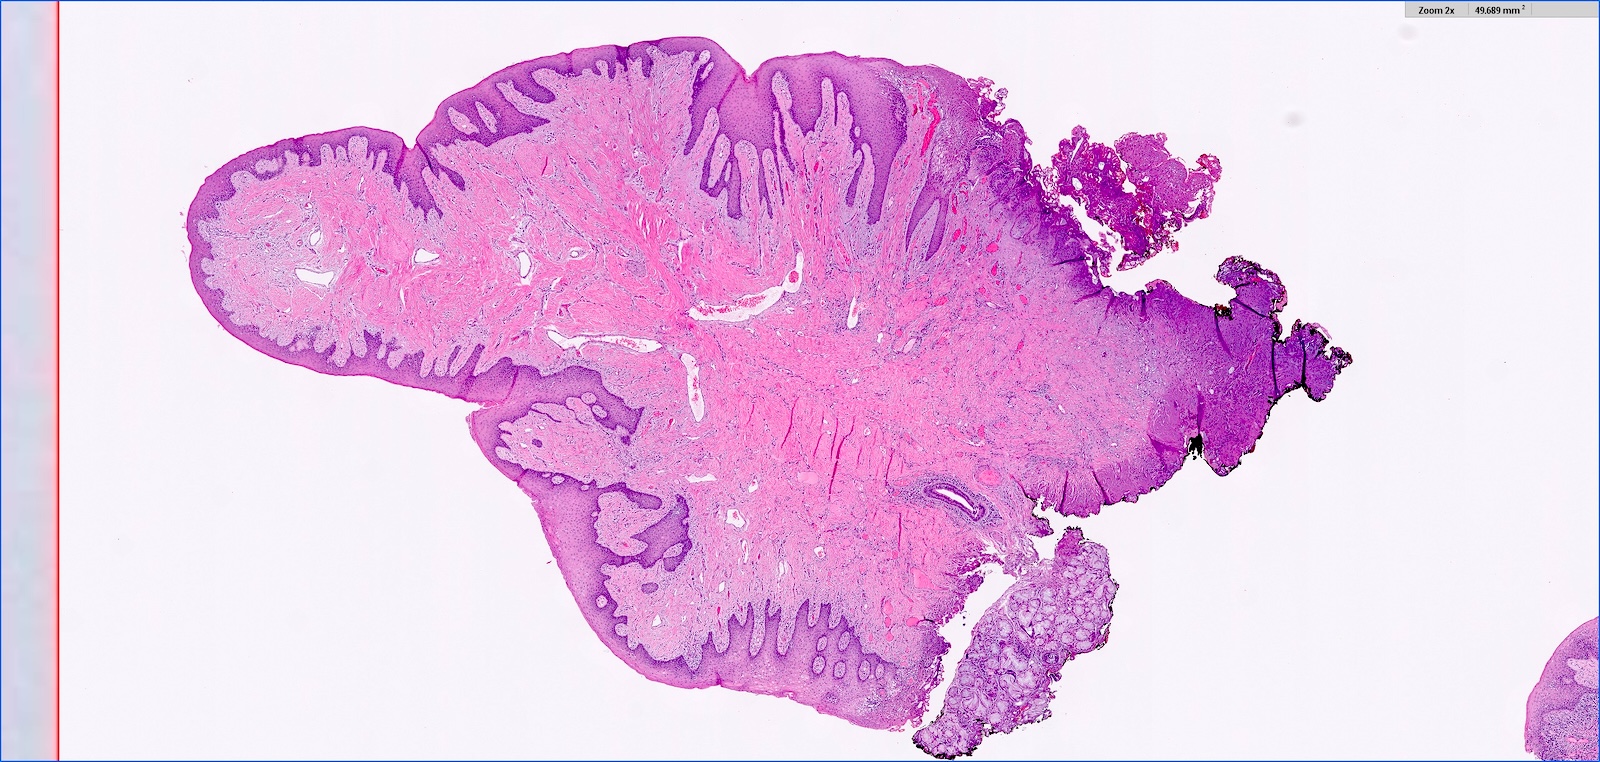

- Hyperplastic keratinized squamous mucosa overlying dense nodular connective tissue and variable inflammatory infiltrate (Acta Histochem 2016;118:451, Head Neck Pathol 2019;13:103)

- Underlying connective tissue is variably collagenized with scant bland spindled fibroblasts (Head Neck Pathol 2019;13:103)

- Pseudoepitheliomatous hyperplasia or secondary candidal colonization may be present

C. Inflammatory fibrous hyperplasia. The image shows squamous mucosa overlying a dense collagenous proliferation with focal chronic inflammation. Answer A is incorrect because amyloidosis is an accumulation of an acellular eosinophilic amorphous material in the submucosa. Answer B is incorrect because giant cell fibroma is not related to a history of chronic irritation. Morphologically the submucosa contains numerous stellate fibroblasts that can be multinucleated. Answer D is incorrect because solitary fibrous tumor is a cellular and vascular neoplastic proliferation; it does not have abundant reactive collagen.